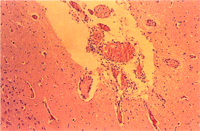

4. 腸:結腸之腸系膜盤繞部呈膠樣水腫,大腸黏膜面鈕扣狀潰瘍灶(圖1) 。